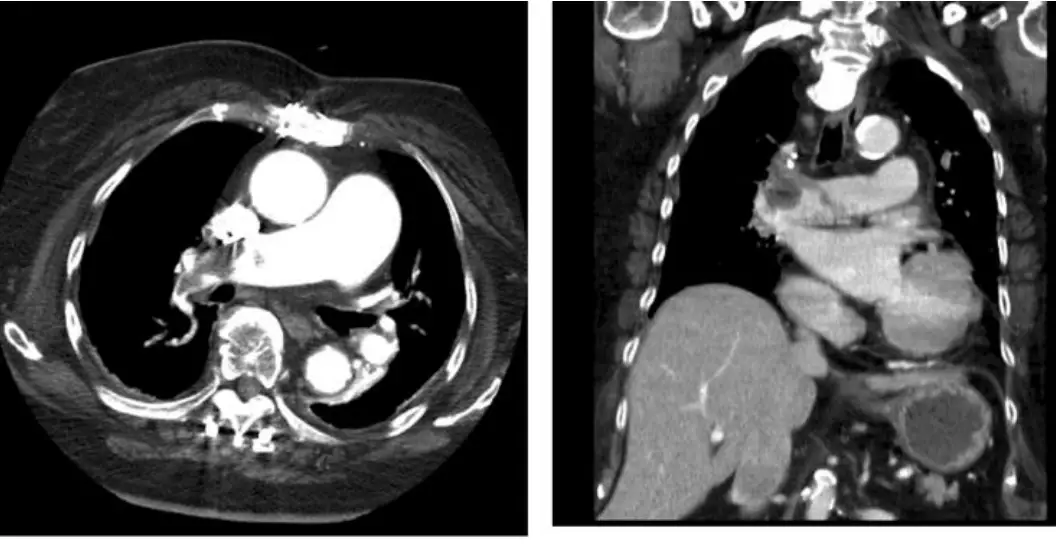

圖一:胸部電腦斷層血管攝影(CT Pulmonary Angiography, CTPA)

本圖包含橫軸位(axial)及冠狀位(coronal)兩個切面:

- 橫軸位(左圖):可見右側肺動脈主幹及左肺動脈內有明顯充填缺損(filling defect),對比劑無法進入栓塞部位,呈現低密度區域;右心室明顯擴大,右室/左室比例增大,顯示右心壓力負荷增加(right heart strain)。

- 冠狀位(右圖):進一步確認雙側肺動脈栓塞範圍廣泛,屬於鞍型栓塞(saddle embolism)或雙側主幹 PE 的型態;可見右心房、右心室擴張,提示急性肺心症(acute cor pulmonale)。